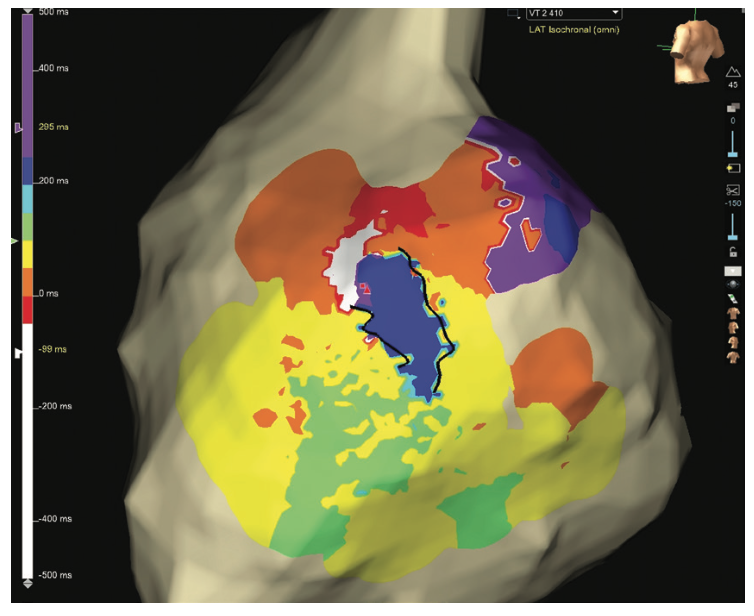

Reinduction was then attempted to gather more data on the activation map, but a different VT was induced. This VT was also not well tolerated hemodynamically, but limited mapping in the same region showed a circuit utilizing a similar isthmus, just in reverse (Figure 8, Video 3).

Video 3. Limited inverse propagation map of VT 2. The black lines show the boundaries of the critical isthmus.